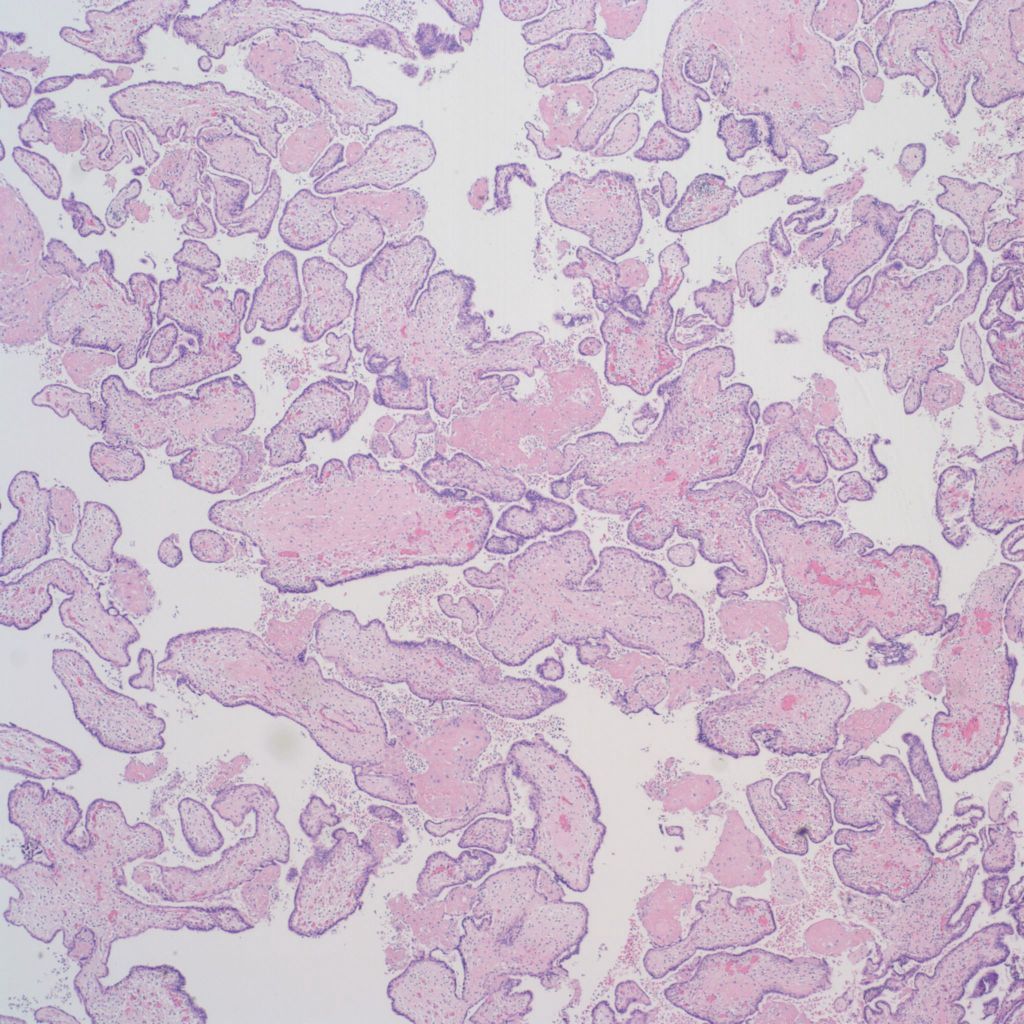

CHIV associated with Villitis of Uknown Etiology (VUE)

This pattern could be due to a primary cause of VUE with incidental chemotaxis of monocytes, two pathogenetically interrelated processes, or an incidental focus of VUE in a predominant CIIV disease. Currently, describing the extent of each process and its colocalization or lack of may prove useful until a better way to classify the co-existing lesions can be developed. One study has shown that there is a dichotomy between cases with c4d staining and those without c4d staining18.